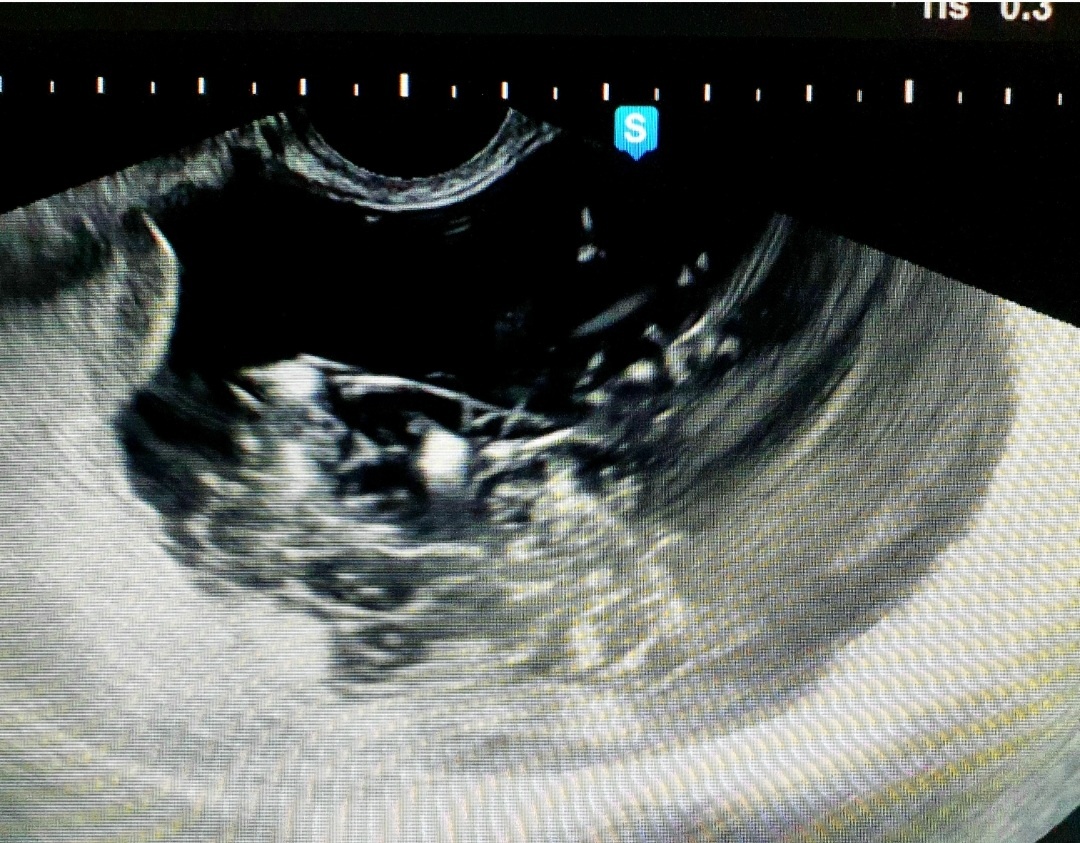

По УЗИ получилась вот такая картина.

Фото из личного архива.

Мы видим округлое образование с чёткими контурами с жидкостным неоднородным содержимым.

Размеры образования 10,0×10,0×9,0 см.

На фоне жидкостного компонента видны множественные линейные тонкие светлые линии и по периферии светлые небольшие образования.

Предположительно это тератома

( дермоидная киста).

Можно предположить, что линейные структуры- это волосы , светлые фрагменты- жировая ткань. Эта картина поразила тем, что так чётко волосы внутри кисты я видела впервые!